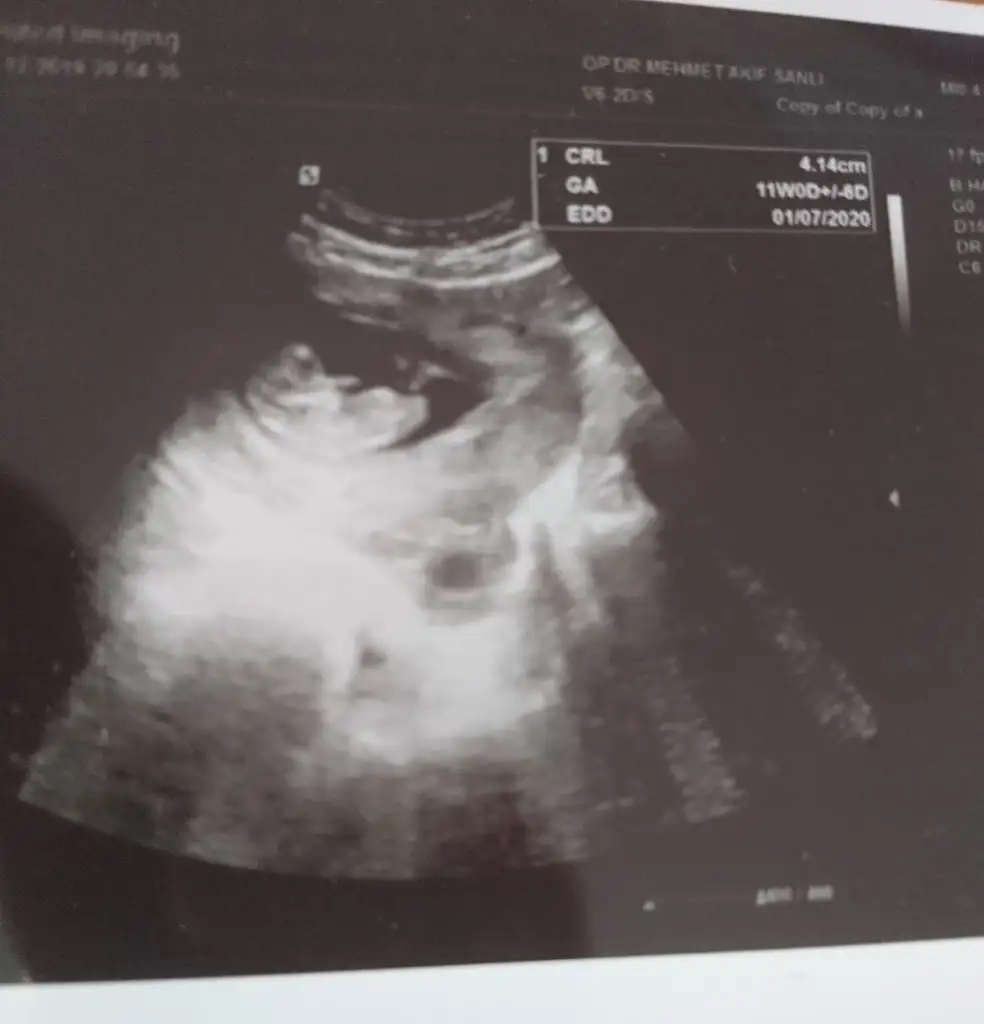

Net degil görüntüyü tek ve yakın alın sanki kız eminde degilimRica etsem bana da bakabilir misiniz? 11 haftalık

Rica etsem bana da bakabilir misiniz? 11 haftalık

Net degil görüntüyü tek ve yakın alın sanki kız eminde degilim